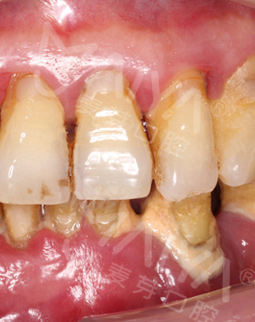

麦芽的博士专家团在看过我的片子后发现,我的牙齿由于长期对口腔疏于护理,牙周情况非常差,余牙有些松动,且牙槽骨萎缩严重,现存的骨量无法进行传统的种植牙手术,因此给我设计了“all-on-4”种牙技术的升级版本“all-on-5”,前期是要处理我的牙周问题,当天就给安排了洁牙,然后上药,等牙周恢复差不多就可以进行种植了!

经过一个月的牙周治疗,牙齿肿胀部分都已经消退,来麦芽种牙之前,心理还有点小紧张,总害怕种牙特别疼,恢复时间慢。我的牙齿情况比较复杂,部分牙齿有牙槽骨吸收,经过前期的各种检查,医生说我的身体状况适合种牙。